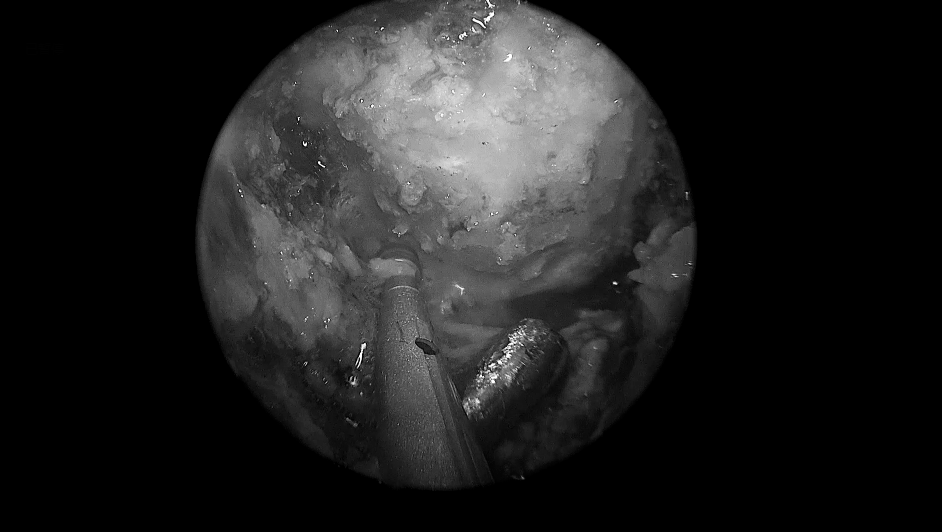

将肿瘤分离出来——Basilar Artery,基底动脉;Left VA,左侧椎动脉; Right VA,右侧椎动脉;

肿瘤取出后,可见清晰的周围血管神经。R VI,右侧展神经;LVI,左侧展神经;R AICA,右侧小脑下前动脉;L AICA,左小脑下前动脉;R VA,右侧椎动脉;LVA,左侧椎动脉;Basilar ,基底

VI,展神经;VII,面神经;VIII,前庭蜗神经;R AICA,右侧小脑下前动脉;